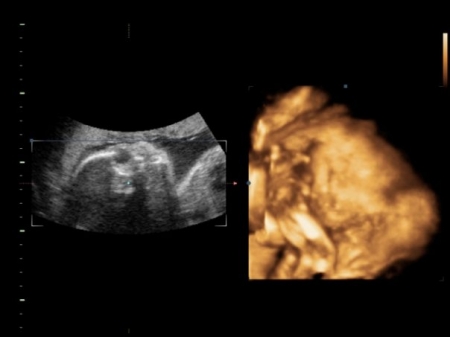

3. Jak vypadá miminko 26. týden těhotenství?

Miminko měří od temene k zadečku 26. týden těhotenství asi 23 cm a váží asi 850 g.